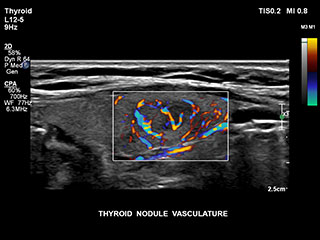

Получение информации о кровотоке в мелких сосудистых структурах с небольшим кровотоком традиционно считается сложной задачей. Благодаря новой функции MicroCPA в системе EPIQ визуализация капиллярного кровообращения с низкой скоростью кровотока выполняется быстро и просто, обеспечивая более точную диагностику при оценке перфузии органов и сети небольших сосудов.